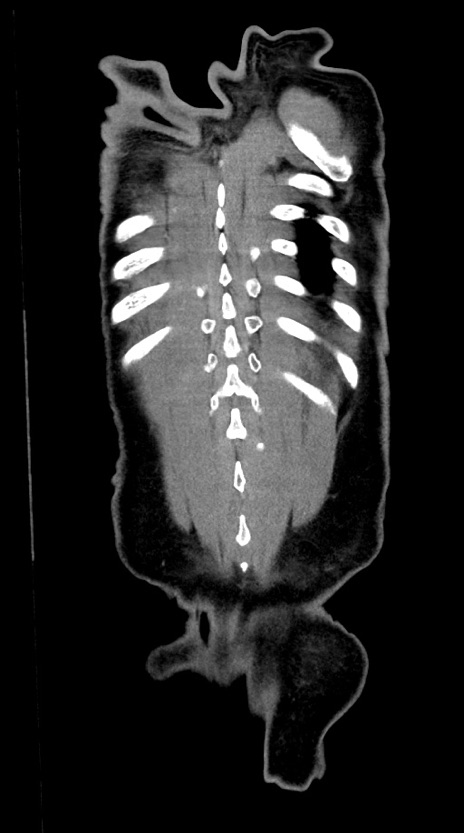

横断像

【症例】60歳代男性

【現病歴】胃癌にて胃全摘後。食思不振が悪化し、夜中に嘔吐することがある。

【既往歴】胃癌、胃全摘、脾摘、胆摘後